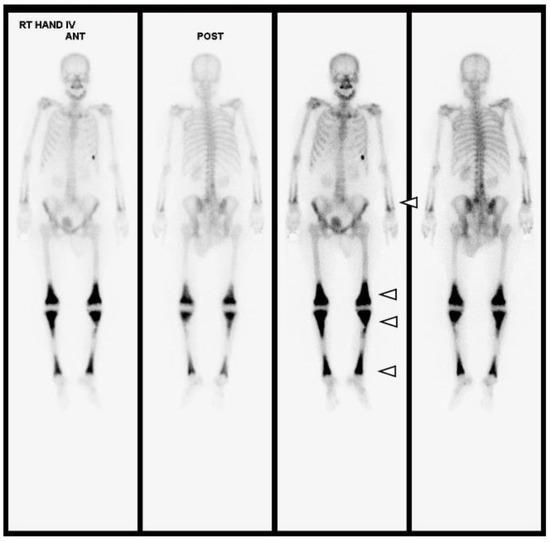

Figure 6.

Upon whole-body bone scanning (Tc-99m HDP Bone Scintigraphy), there is intense, bilaterally symmetric uptake at the end of long bones, such as both tibias, femurs, radii and ulnas, with sparing of the epiphysis, which is characteristic of ECD (white arrowheads). Differential diagnoses of other osteosclerotic conditions include diseases such as lymphoma, chronic osteomyelitis, Paget’s disease, or metastases; however, amongst these, symmetrical metadiaphyseal uptake on nuclear scintigraphy is exclusive to ECD.